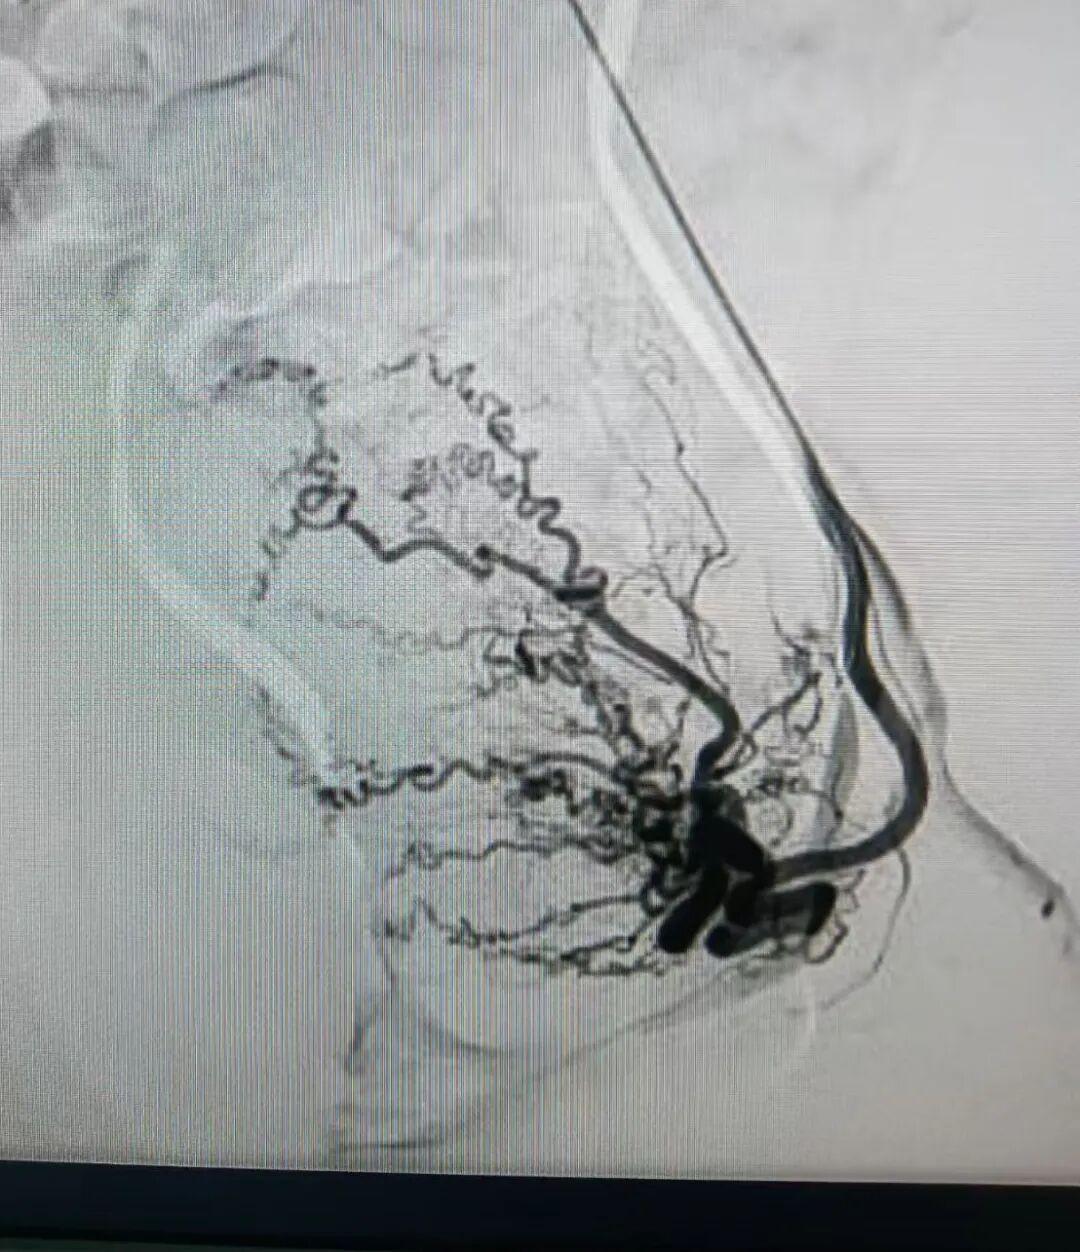

近日,洛阳白马医院介入科团队为患者成功施行了经远端桡动脉子宫动脉造影及栓塞术。手术仅在远端桡动脉处建立微小穿刺口,将导管精准送至子宫动脉。通过造影明确病灶的供血血管后,团队注入栓塞剂,阻断病灶血流,使异位内膜组织因缺血而逐渐萎缩,从而达到缓解疼痛、减少出血的目的。

子宫动脉栓塞术是一种血管性介入治疗方法,其原理是通过"堵血管"的方式,切断子宫腺肌病灶的血供。医生在患者一侧的大腿根部或手腕处用细针穿刺,仅留下一个微小的针眼,然后将导管在X光血管造影机的引导下,精准送达子宫动脉,注入栓塞颗粒,阻断病灶的血流供应。失去血供的病灶组织会逐渐缺血坏死、萎缩,从而缓解疼痛、减少月经量,达到治疗目的。

洛阳白马医院作为一家二级非营利性综合医院,自1959年建院以来,始终秉持"以患者为中心"的服务理念。近年来,医院不断推进技术升级,已成功开展多项介入微创手术。医院配备了先进的飞利浦血管造影系统(DSA),能够提供高清的血管成像,使医生能够更精准地定位子宫动脉,确保手术的精确性和安全性。